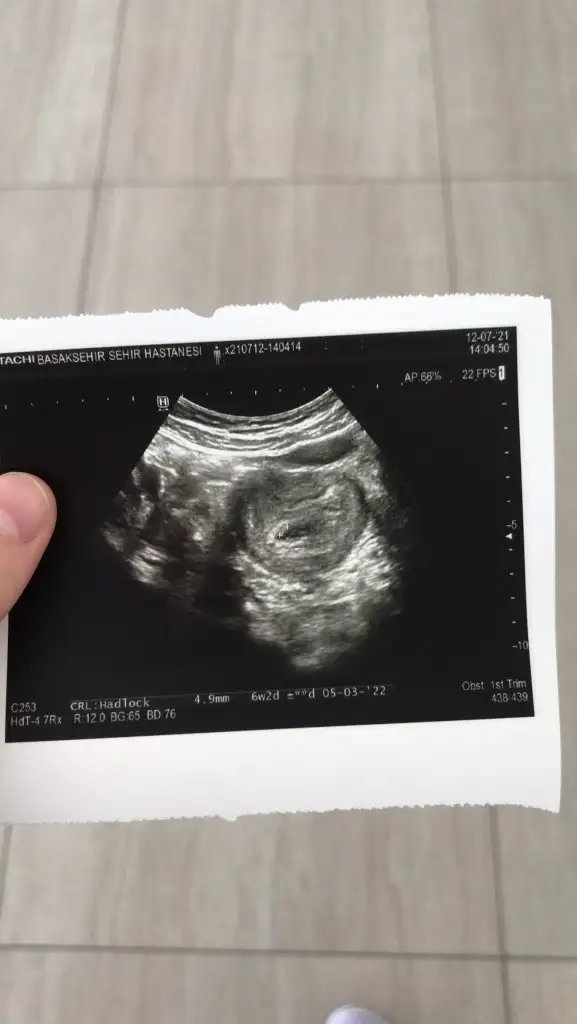

Maşallah gözün aydın. Darısı bizlere olsun inşallah. Sat kaçtı senin?Merhaba kızlar bugün sonunda doktora gittim keseyi de bebeği de gördü kalp atışını duydu sata göre tam 6 hafta bitti 6+2 gözüküyor haftanla uyumlu dedi çok şükür

Resim ekledim ama becerebilmiş miyimdir bilmiyorum

MerhabaMerhaba kızlar bugün sonunda doktora gittim keseyi de bebeği de gördü kalp atışını duydu sata göre tam 6 hafta bitti 6+2 gözüküyor haftanla uyumlu dedi çok şükür